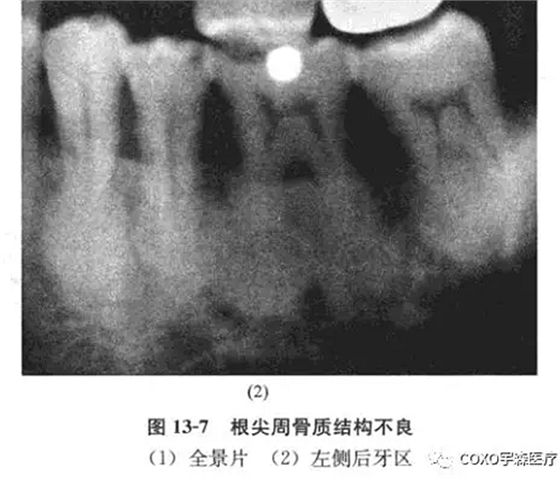

x線片示:雙側(cè)后牙區(qū)高密度陰影(圖13-7),初步診斷:雙側(cè)后牙區(qū)根尖周骨質(zhì)結(jié)構(gòu)異常,伴感染,收入院。